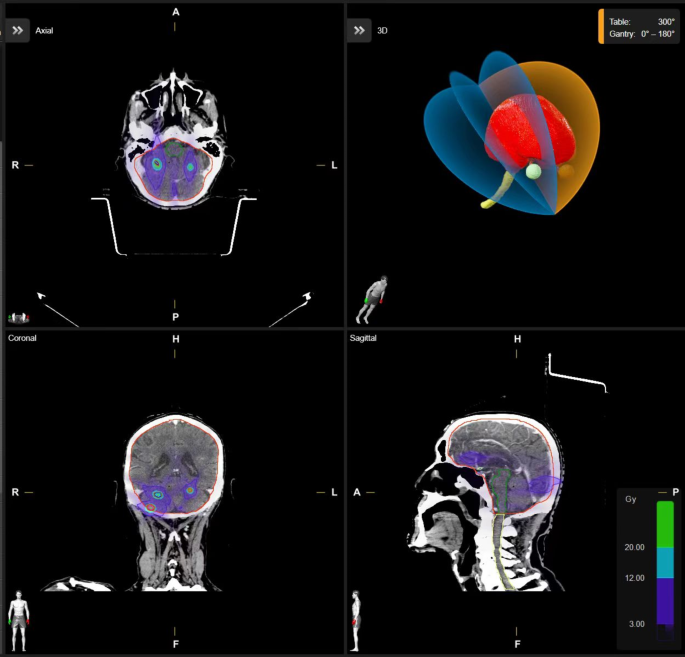

HA external beam planning was conducted in Eclipse utilizing analytic anisotropic algorithm (AAA) with a calculation voxel size of 1 mm. The SRS support structure model Encompass was to match the immobilization device. PTVs were set to high resolution structures in contouring. Partial arc treatment was utilized when the isocenter was located outside the patient protection zone, while full arc treatment was utilized if it was located inside. Normal tissue objective value was optimized to protect critical structures. All doses were corrected for heterogeneity on the 1.25 mm grid size. Figure 1 shows an example of a plan generated on HA.

Elements MBM was calculated with Pencil Beam followed by Monte Carlo algorithm with a calculation voxel size of 1 mm, following that of HA. A tissue model was generated for each case under Couch Top of Frameless Extension. For the gantry and table optimization protocol, a maximum of 2 passes and 4 extra arcs were allowed. A minimum of 4 table angles were assigned, with a maximum of 5 table angles allowed. Automatic Arc Setup Mirroring, Automatic Table Angle Optimization, and Automatic Gantry Angle Optimization were enabled for greater flexibility. Figure 2 shows an example of a plan generated on Brainlab Elements MBM.